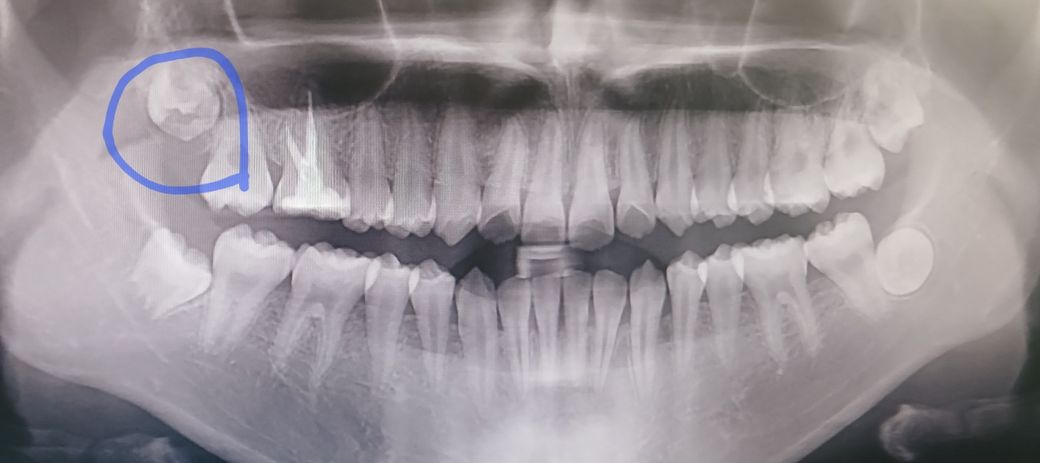

제가 16번 어금니 신경치료 후 크라운을 씌웠는데, 만약 나중에 발치를 하게 된다면 임플란트 없이 제 사랑니로 대체 가능한 지 궁금해요. 사랑니가 좀 작은 거 같은데 언제쯤 다른 치아처럼 형태를 갖출까요? 사랑니 잘 나려면 (+관리) 어떻게 해야 하는지 알려주세요. 지금 19세라 사랑니 잘 자랄 수 있겠죠? 발치하면 가랑니로 대체하고 싶은데.....ㅠㅠ

• 1번 째 사진

1. 이미 사랑니 형태는 갖춰졌고 바뀌진 않습니다. 어금니와는 조금 다른 모습일 수 있습니다.

2. 아직까지 오른쪽 위 사랑니는 잇몸뼈 안에 묻혀있고 특별히 해줄 수 있는 건 없습니다.